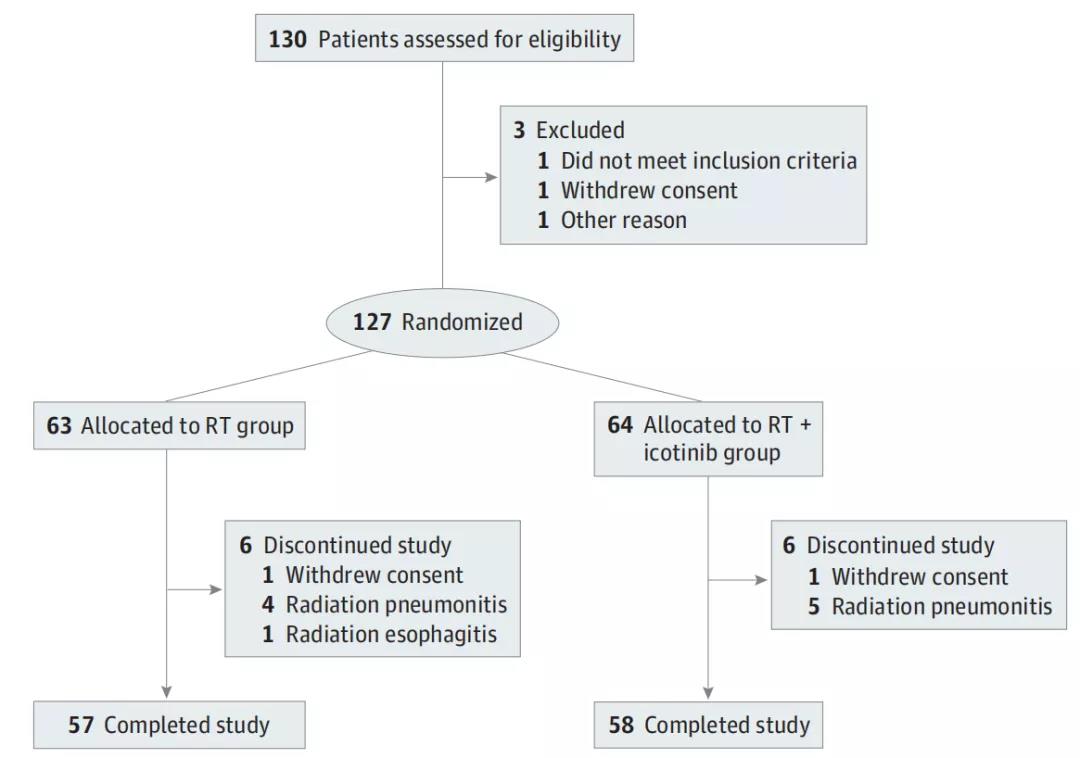

近期,中国医学科学院肿瘤医院深圳医院放射治疗科的吴式琇教授等在JAMA Network Open发表一项研究,结果显示,与单纯放疗相比,埃克替尼联合放疗可提高不可...